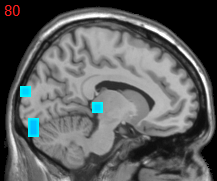

Usually, the first step of voxel-based neuroimage analysis requires preprocessing the T1-weighted image, such as segmentation and registration of grey matter (GM), white matter (WM) and cerebral spinal fluid (CSF). However, some systematic biases due to scanner difference and different population etc., can be introduced in this pipeline [2]. Part of them can be helpful to the discrimination of subjects from normal controls (NC), but may not be directly related to the disease. For example in structural Magnetic Resonance Imaging (sMRI) images of subjects with Alzheimer’s Disease (AD), after spatial normalization during simultaneous registration of GM, WM and CSF, the GM voxels surrounding lateral ventricle and subarachnoid space etc. may be mistakenly enlarged caused by the enlargement of CSF space in those locations [2] compared to normal template, as shown in Fig. 1. Although these voxels/features are highly correlated with disease, they can’t be regarded as lesion features in an interpretable model. In this paper we refer to them as “Procedural Bias”, which should be identified but is neglected in the literature. We observe that it can be harnessed in our voxel-based image analysis to improve the prediction of disease.

Figure 1: The overlapped voxels among top 150 negative value voxels in each fold of βpresubscript𝛽𝑝𝑟𝑒\beta_{pre} at the time corresponding to the best average prediction result in the path of GSplit LBI using 10-fold cross-validation. For subjects with AD, they represent enlarged GM voxels surrounding lateral ventricle, subarachnoid space, edge of gyrus, etc.

The process of feature selection combined with prediction accuracy can be analyzed together along the path. The result of 30ADNC is used as an illustration in Fig. 3. We can see that βpresubscript𝛽𝑝𝑟𝑒\beta_{pre} (blue curve) outperforms βlessubscript𝛽𝑙𝑒𝑠\beta_{les} (red curve) in the whole path for additional procedural bias captured by βpresubscript𝛽𝑝𝑟𝑒\beta_{pre}. Specifically, at βpresubscript𝛽𝑝𝑟𝑒\beta_{pre}’s highest accuracy (t5subscript𝑡5t_{5}), there is a more than 8%percent88\% increase in prediction accuracy by βpresubscript𝛽𝑝𝑟𝑒\beta_{pre}. Early stopping regularization at t5subscript𝑡5t_{5} is desired, as βpresubscript𝛽𝑝𝑟𝑒\beta_{pre} converges to βlessubscript𝛽𝑙𝑒𝑠\beta_{les} in prediction accuracy with overfitting when t𝑡t grows. Recall that positive (negative) features represent degenerate (enlarged) voxels. In each fold of βpresubscript𝛽𝑝𝑟𝑒\beta_{pre} at t5subscript𝑡5t_{5}, the commonly selected voxels among top 150 negative (enlargement) voxels are identified as procedural bias shown in Fig. 1, where most of these GM voxels are enlarged and located near lateral ventricle or subarachnoid space etc., possibly due to enlargement of CSF space in those locations that are different from the lesion features.